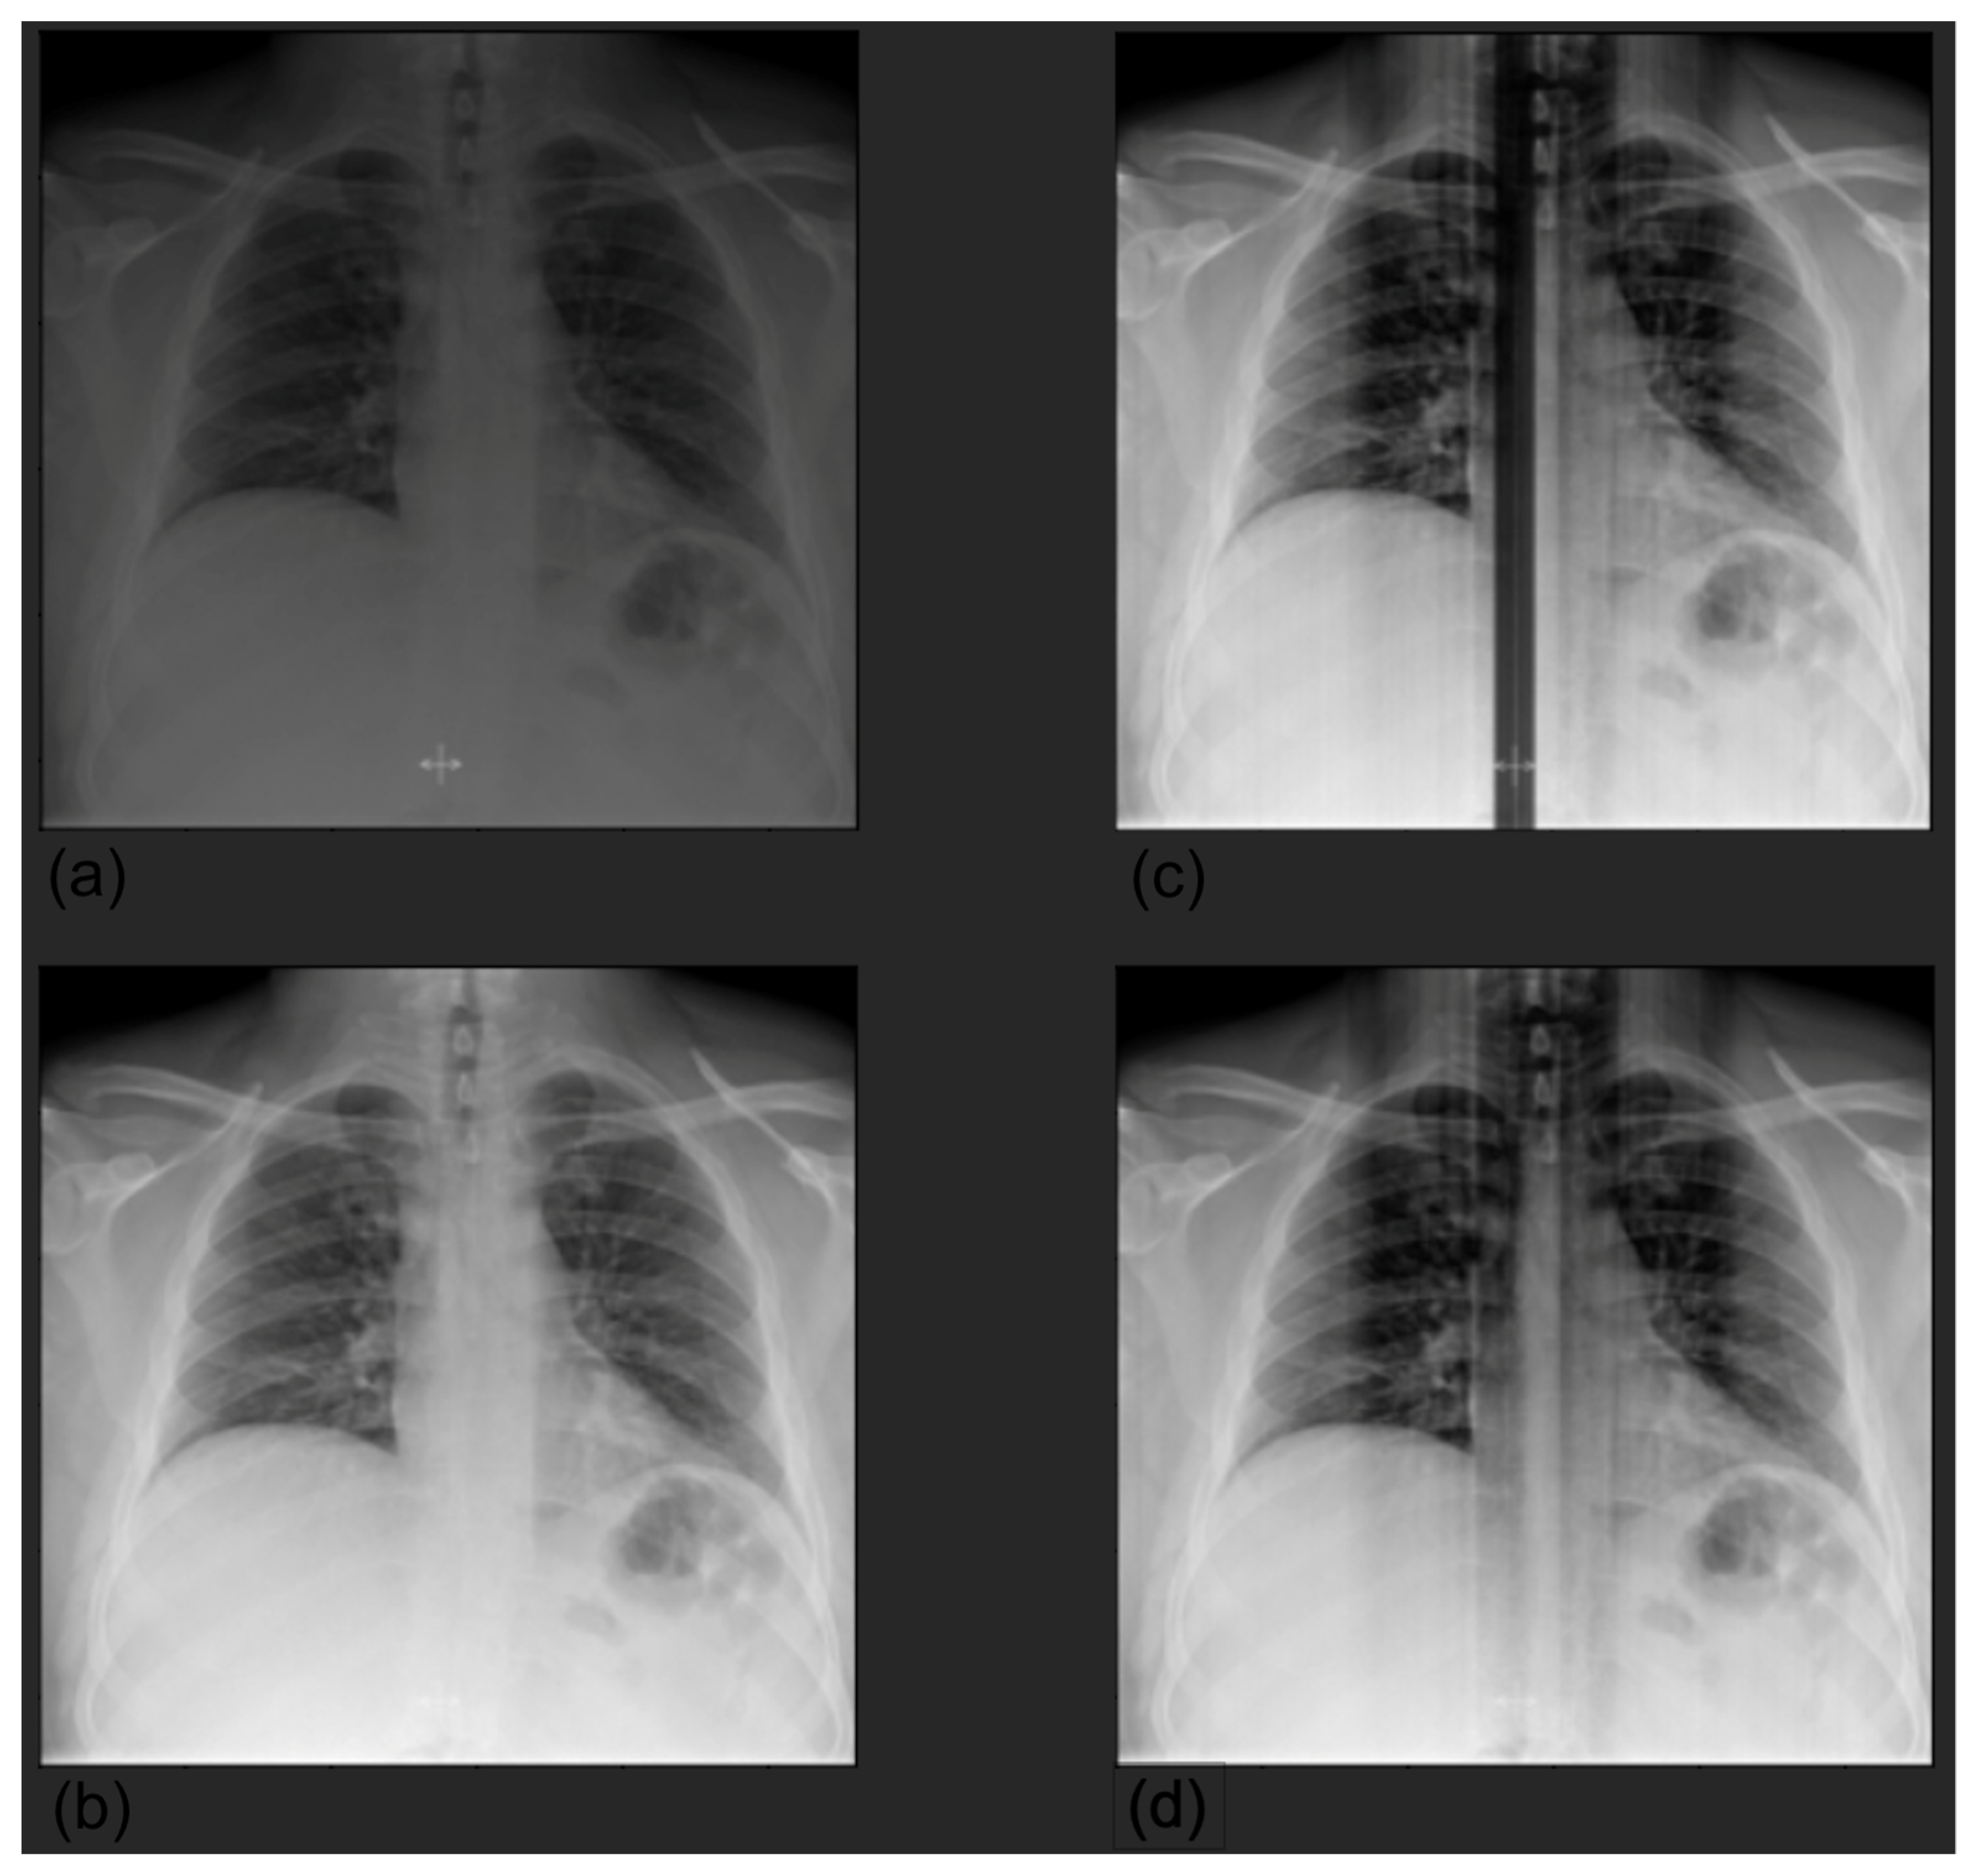

2.1. Datasets

2.2. Pretraining on CheXpert